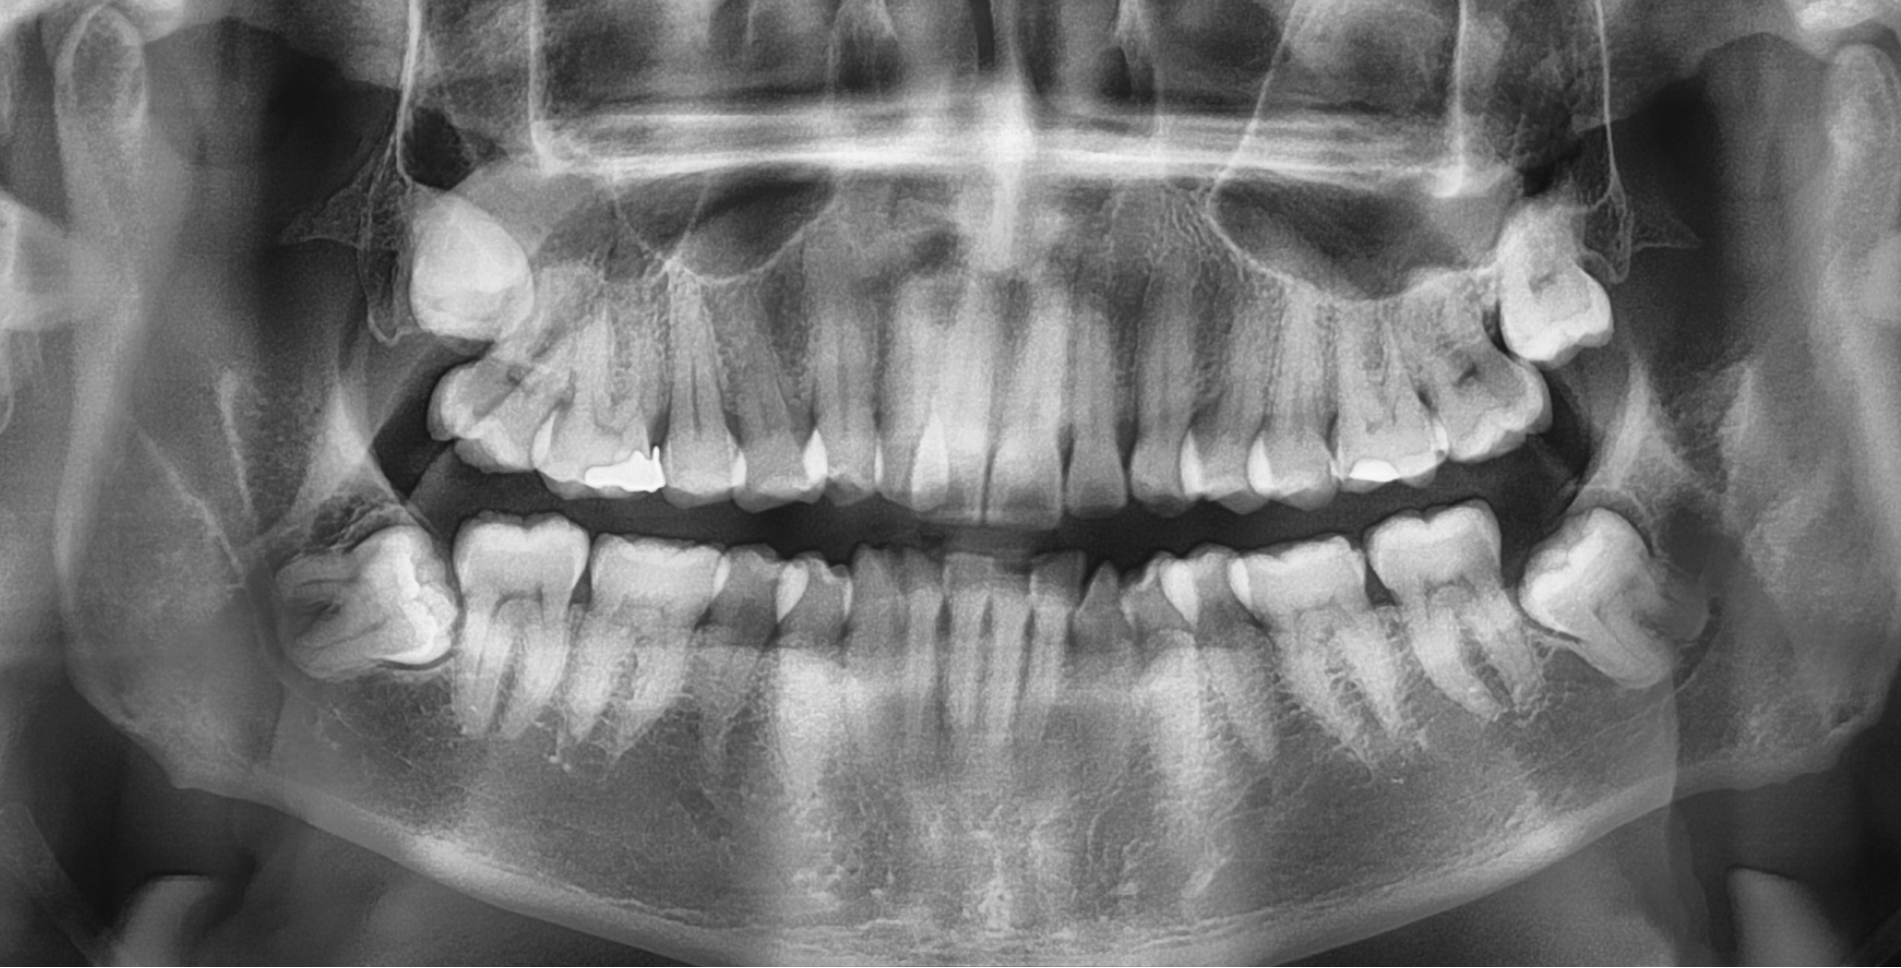

The main reason you may need to see an Oral Surgeon is for impacted wisdom teeth. While the majority of wisdom teeth erupt into the mouth uneventfully between the ages of 18-25 this is not always the case.

Sometimes wisdom teeth do not have suffiecient room to erupt fully, these are called impacted. Impacted teeth can sometimes lead to painful infections as well as food packing, which in turn can lead to decay. Sometimes this decay is in the adjacent tooth.